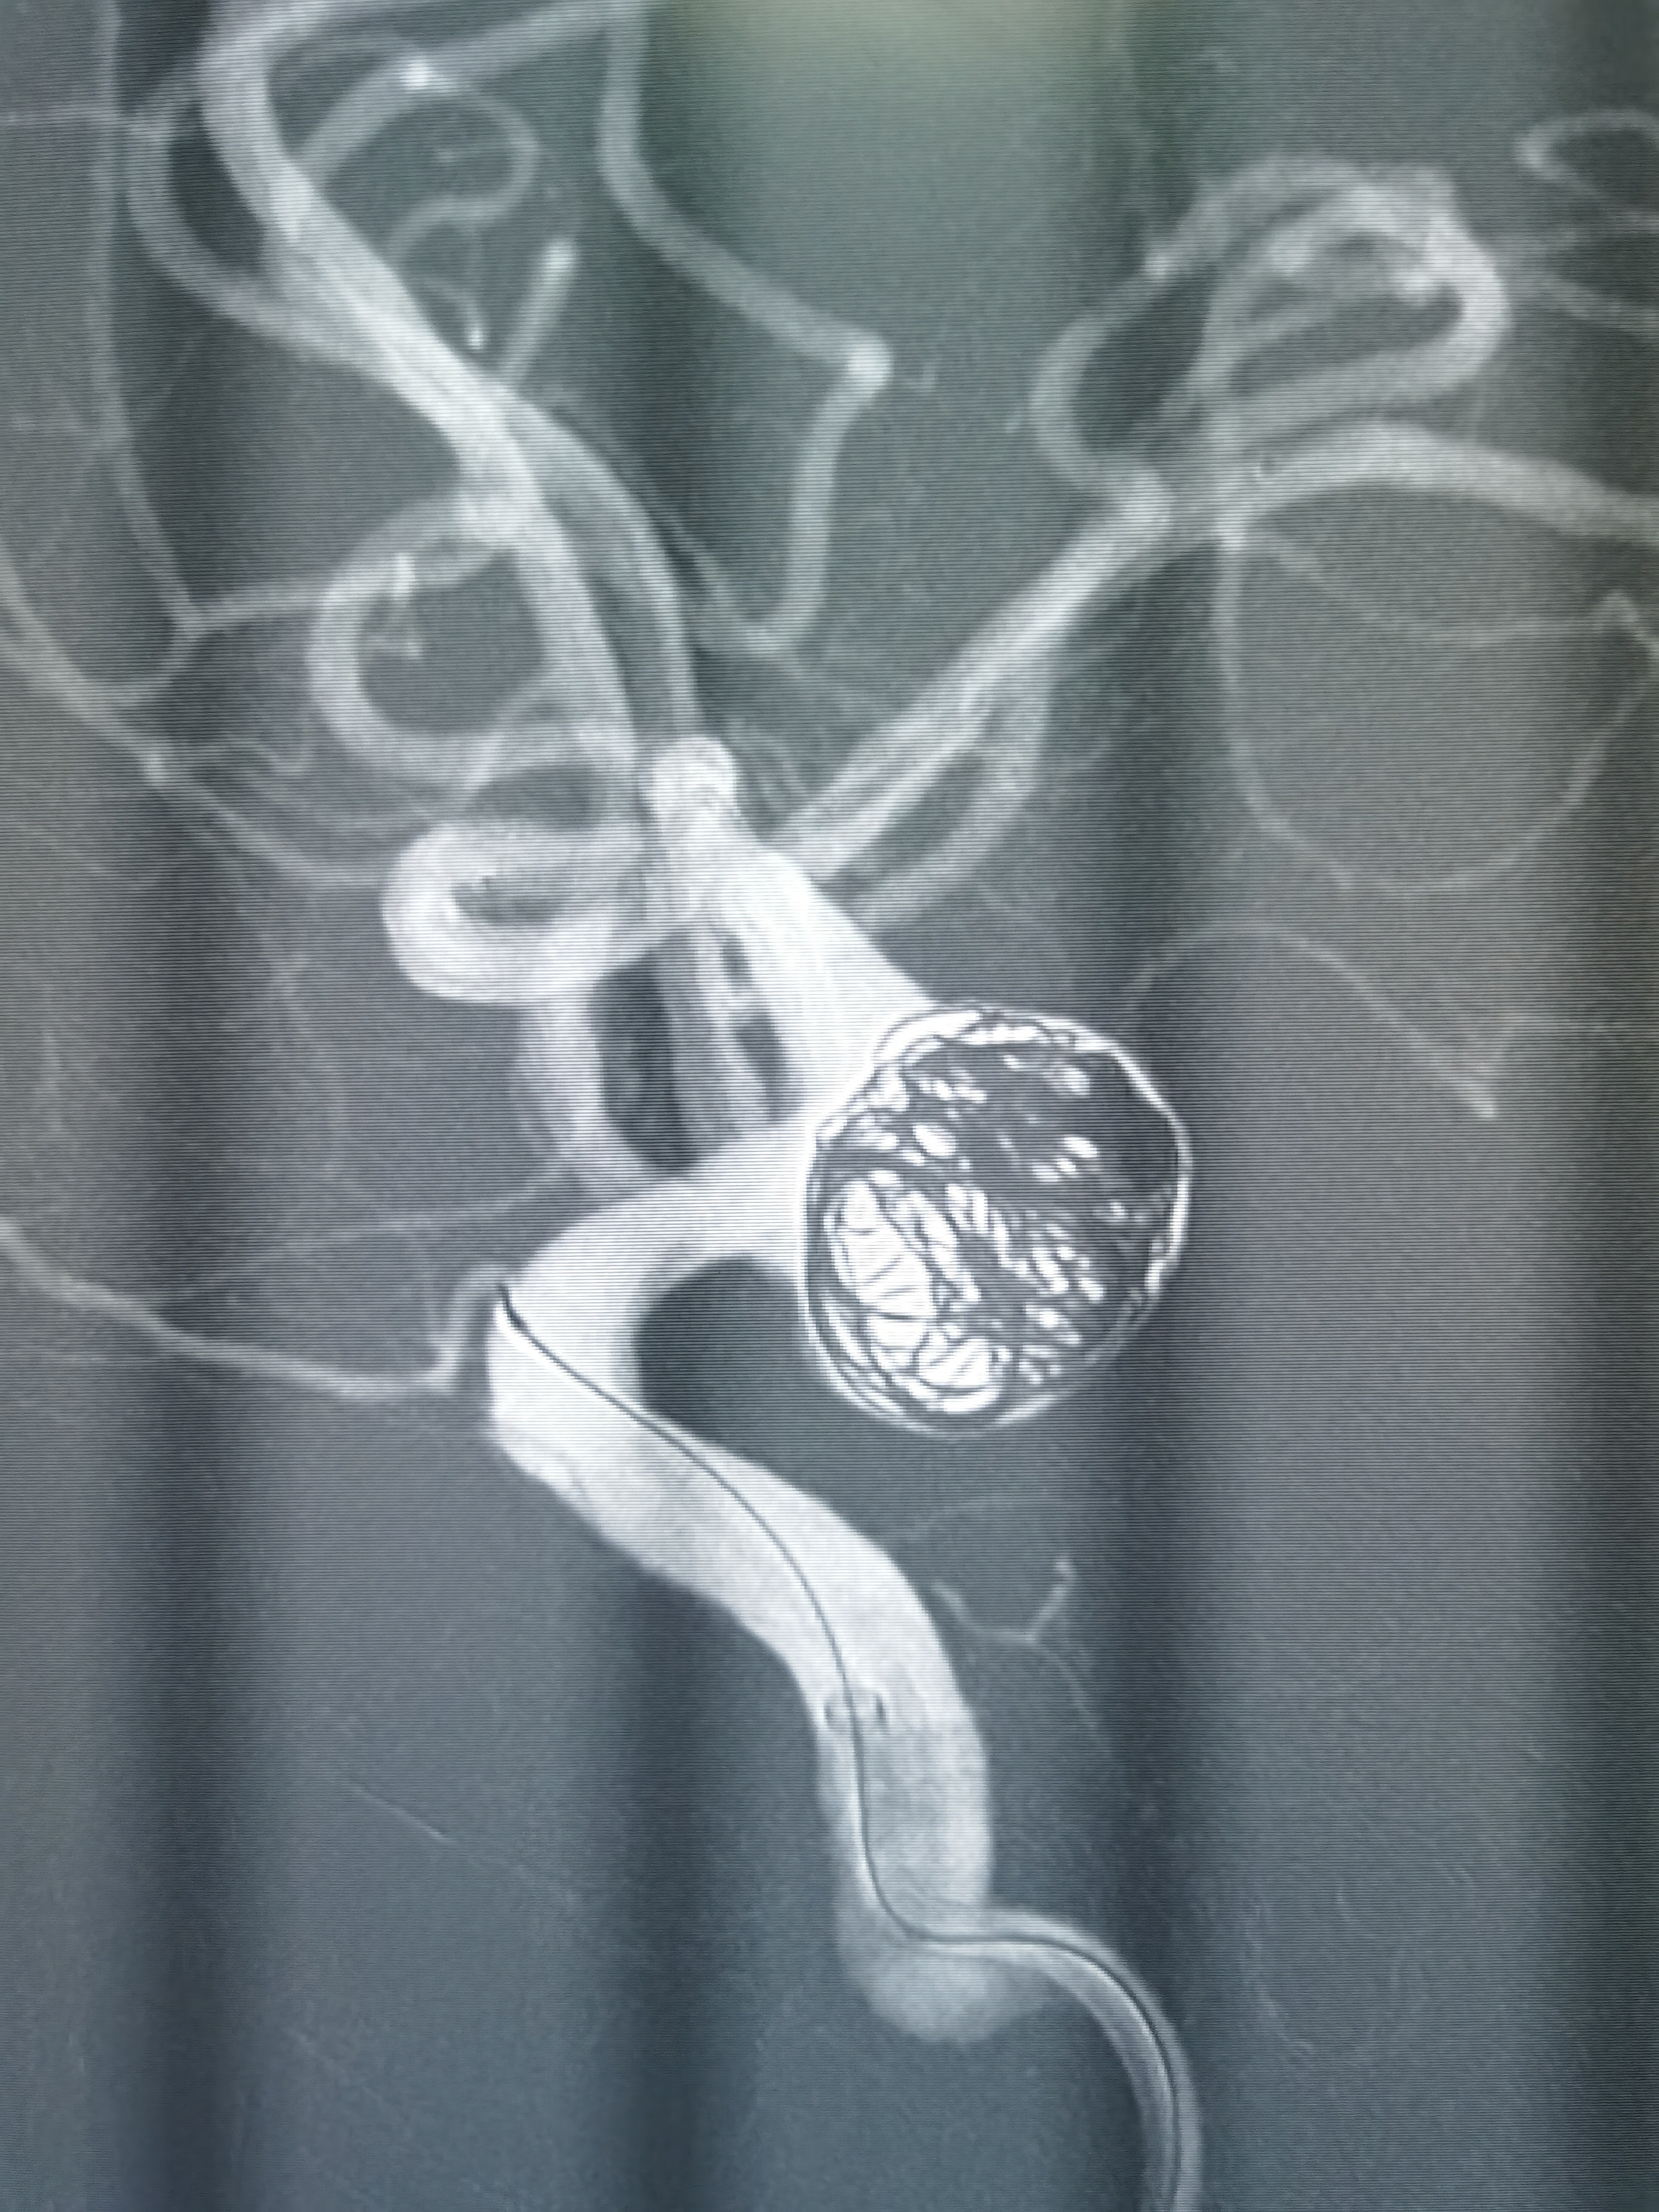

微导管塑形后送入动脉瘤腔内,首枚填入12*30成蓝圈,再依次填入10*30,9*30,8*30弹簧圈,造影见瘤体上部致密填塞,载瘤动脉通畅。

利用微导丝将栓塞微导管再重新选入动脉瘤体下部,依次填入7*30,7*20弹簧圈,复查造影见动脉瘤大部填塞,瘤内造影剂滞留明显载瘤动脉通畅。

术后即刻造影见动脉瘤栓塞较完全。

术后造影见动脉瘤栓塞较为完全,载瘤动脉通畅,遂未再植入支架,逐渐撤出各级导管,缝合股动脉结束手术。